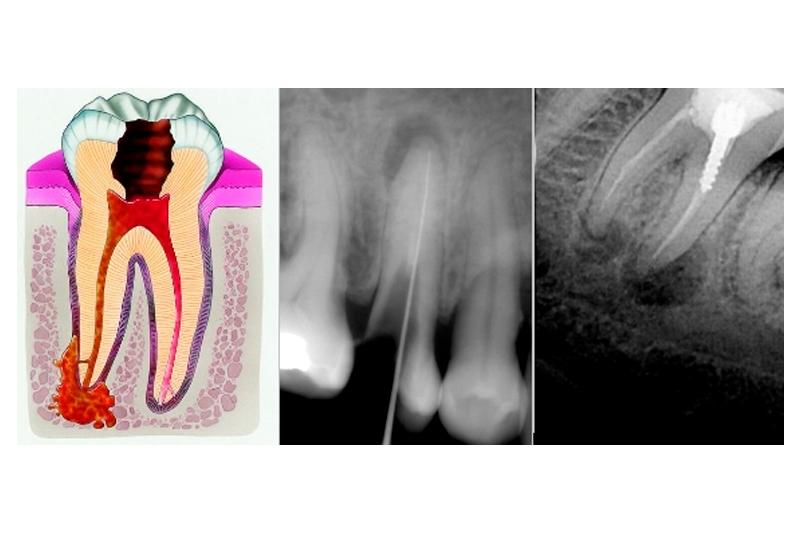

Причиной периодонтита могут быть инфекция, травма, действие токсичных веществ. Чаще периодонтит является исходом кариеса или пульпита, при котором пульпа (нерв) уже не может служить барьером для токсичных продуктов и они проникают за верхушку зуба. Периодонтит как и пульпит в большинстве случаев развивается на начальных стадиях практически незаметно, зачастую после острого воспаления пульпы и при отсутствии соответствующего лечения.

При длительном течении процесса околоверхушечная костная ткань постепенно разрушается, образующийся дефект замещается грануляционной тканью.

В одних случаях у больного вокруг грануляционной ткани образуется плотная фиброзная капсула — зубная гранулема, которая со временем может превратиться в кисту, заполненную гноем и продуктами воспаления.

В других, возникает очаг, постоянно генерирующий гной, что приводит к формированию на десне в области проекции корня больного зуба длительно функционирующего свища.

Периодонтит является следующей стадией развития пульпита.

Воспаление периодонта возникает от многих причин: в результате осложнения пульпита или его непрофессионального лечения, поражения, в результате травмы или длительного воздействия препаратов, содержащих мышьяк, на зубную полость.

Периодонтит — это опасное заболевание представляет собой воспаление корневой части зуба и прилегающих к ней мягких тканей.